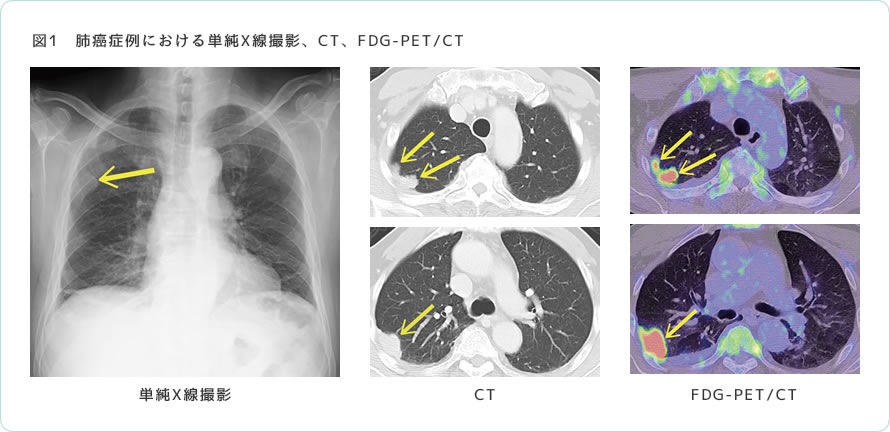

PET-CT画像診断マニュアル Clinical PET and PET/CT | SpringerLinkの詳細情報

Clinical PET and PET/CT | SpringerLink。fmed-09-896494-g001.jpg。医療関係のみなさまへ 日本医科大学健診医療センター。 現在、1名がこの商品を検討中です

PET-CT画像診断マニュアル

PET-CT画像診断マニュアル